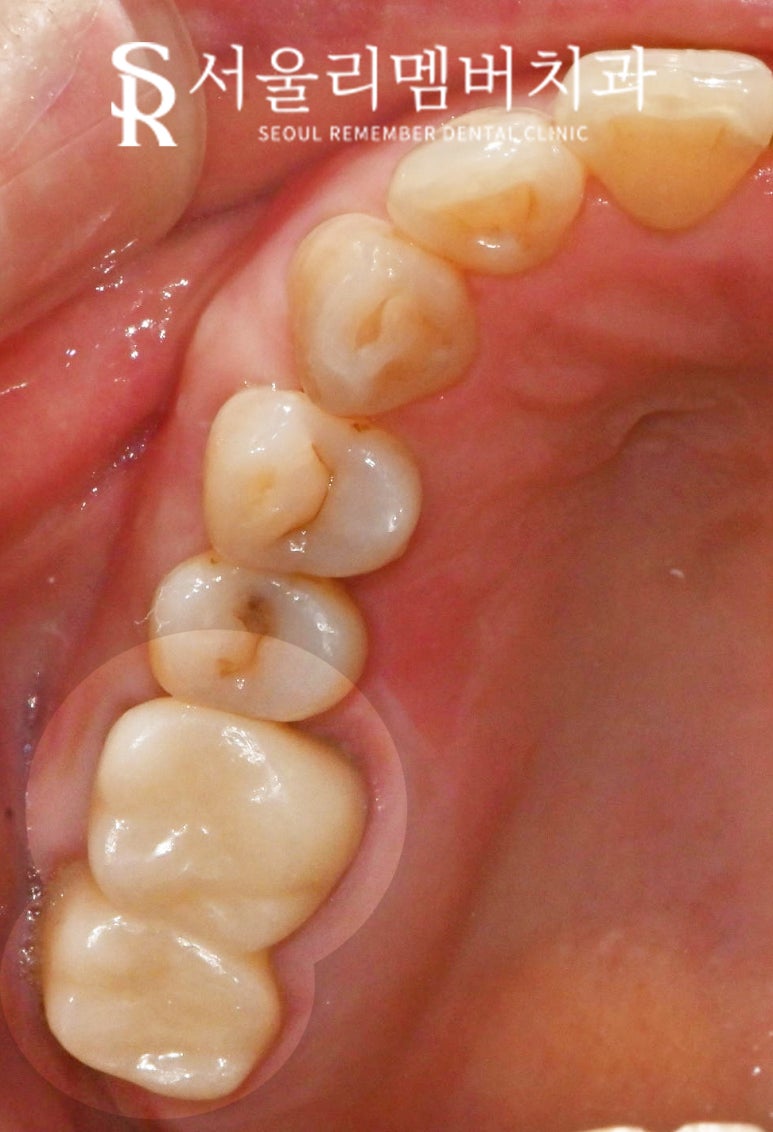

구내 사진을 보면

상악 좌측 구치부의 25번이

PFM으로 수복된 것을 볼 수 있습니다.

PFM 이란 내부는 금속 소재로 이루어져 있고

겉은 도자기로 덮여있는 보철의 한 종류인데요,

시간이 지날수록

바깥을 둘러싸고 있는

도자기 소재의 재료가 닳으면서

안쪽의 금속이 보이는 단점이 있습니다.

이것은 교합면에서뿐만 아니라

측면에서 볼 때 치경부 부근에

어두운 그림자가 생기게 할 수도 있다 보니

아마 PFM 크라운을 씌우신 환자들은

이러한 문제 때문에라도

일정 시기가 지나면 교체를 원하시기도 합니다.

오늘 봉천역 치과 에서 보여드리는 증례는

오래된 PFM이 낡고 닳은 것 이외에도

양옆 치아와 틈이 생기다 보니

그 안으로 음식물이 자주 끼는 게

주된 불편감이셨는데요,

한눈에 보기에도

이가 벌어져있는 게 눈에 띕니다.